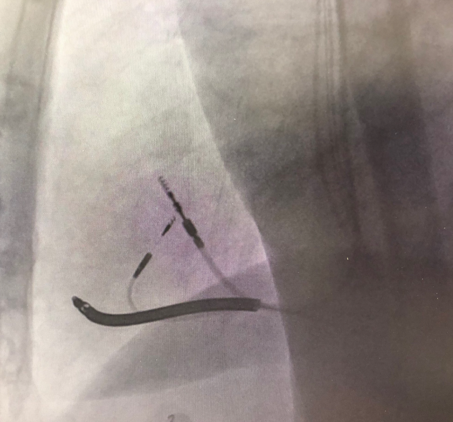

由于明确患者没有合适的靶静脉,薛玉梅主任果断更换手术策略,改行左束支起搏代替左室电极,电极精准放置于左束支区域,起搏图形呈典型左束支起搏,高低电压(1V及5V)达峰时间均为75ms,确定为选择性左束支起搏。起搏阈值仅为0.7V/0.4ms,效果良好;随后心房电极及右室除颤电极均顺利植入,参数良好,在连接好机器后,完美结束手术。

术中手术过程